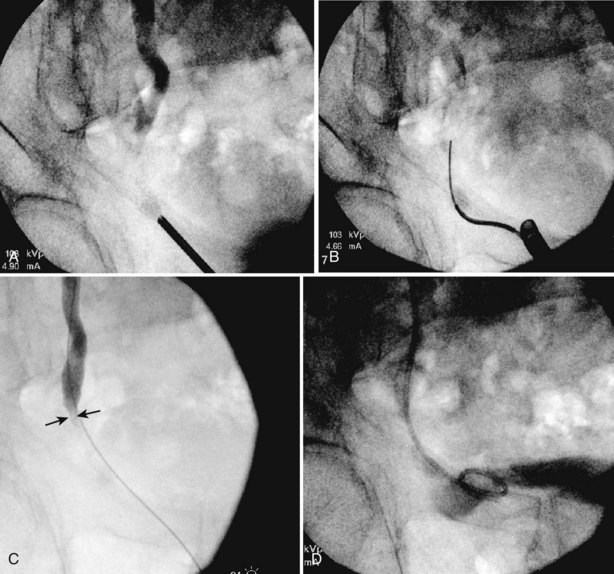

The indications to intervene for any patient with UPJ obstruction include the presence of symptoms, progressive or overall impairment of renal function, development of upper tract stones or infection, or, rarely, causal hypertension. Historically, a percutaneous approach for definitive management of UPJ obstruction was offered only to those patients undergoing percutaneous removal of associated stones or to those who had previously failed open pyeloplasty. However, encouraging results ultimately led many centers to offer percutaneous endopyelotomy as primary therapy for almost any patient with UPJ obstruction. Even with the acceptance of laparoscopic pyeloplasty, percutaneous endopyelotomy is also appropriate for those patients with UPJ obstruction and concomitant pyelocalyceal stones, which can then be managed simultaneously. Contraindications to a percutaneous endopyelotomy are similar to the contraindications to any endourologic approach and include a long segment (>2 cm) of obstruction, active infection, or untreated coagulopathy. Whereas the impact of crossing vessels is controversial, the mere presence of crossing vessels is not a contraindication to an endopyelotomy (Motola et al, 1993b; Nakada et al, 1998; Lam et al, 2003b). However, significant entanglement of the UPJ by crossing vessels can occasionally be identified and this may render any endourologic approach unsuccessful. When such entanglement is suggested by intravenous or retrograde pyelography (Fig. 41–7), it can be reliably verified using three-dimensional helical CT (Kumon et al, 1997).

In the original descriptions of the technique both from the Institute of Urology in London (Ramsay et al, 1984) and from Long Island Jewish Hospital in New York (Badlani et al, 1986), the endopyelotomy was performed using a cold knife technique under direct vision. With one or two wires in place across the UPJ, a direct vision “endopyelotome” is used. This hook-shaped cold knife may be used to completely incise the UPJ in a full-thickness manner, from the ureteral lumen to periureteral and peripelvic fat (Fig. 41–8). Rigorous anatomic studies have shown the incision should generally be made laterally because this is the location devoid of crossing vessels (Sampaio, 1998). However, in cases of high insertion, the incision should instead “marsupialize” the proximal ureter into the renal pelvis, such that an anterior or posterior incision may be required (Fig. 41–9). When such incisions are done under direct vision, any crossing vessel can be directly visualized and avoided. In addition to the endopyelotome, the holmium laser or the cutting balloon catheter may also be used to perform an antegrade endopyelotomy.

Figure 41–9 A, Retrograde study in this patient with left ureteropelvic junction obstruction reveals a “high insertion” of the left ureter. B, CT scan in this same patient reveals the ureter inserting on the anatomically anterior aspect of the renal pelvis. A marsupializing incision must be made in a true posterior direction from the ureter into the renal pelvis.

Use of a cautery wire balloon for management of UPJ obstruction was first reported in a clinical series by Chandhoke and colleagues in 1993. Use of this device gained initial acceptance by many clinicians because standard cystoscopic techniques and real-time fluoroscopy are all that is necessary for its use. Because the procedure is guided fluoroscopically, such vessels may increase the risk of hemorrhage after activation of the cautery wire balloon. Some authors recommended preoperative imaging for such vessels with relatively noninvasive techniques such as CT or three-dimensional CT angiography (Fig. 41–12) (Streem and Geisinger, 1995; Quillin et al, 1996; Nakada et al, 1998; Herts et al, 1999; Nakada, 2000). Nadler and colleagues (1996) reported on 28 patients 2 or more years after cautery wire balloon endopyelotomy. With a mean follow-up of 32.5 months, subjective improvement was noted in 61% of patients, and 81% had a patent UPJ on the basis of diuretic renography or Whitaker testing. More recent studies have demonstrated lower success rates than these initial series (32% to 63%) and perhaps that high-grade hydronephrosis has a negative impact on success (Albani et al, 2004; Sofras et al, 2004). El-Nahas and colleagues reported a small prospective randomized trial comparing retrograde ureteroscopic endopyelotomy to the hot-wire balloon endopyelotomy in 40 patients. Although not statistically significant, they found superior success rates (85% compared with 65%) and lower complication rates with the ureteroscopic endopyelotomy (El-Nahas et al, 2006). Ponsky and Streem reported on 64 patients undergoing either ureteroscopic endopyelotomy or hot wire balloon endopyelotomy and found equivalent success rates with both procedures yet higher major complication rates in the cautery wire balloon endopyelotomy, specifically transfusion and selective embolization (Ponsky and Streem, 2006). The major complication associated with cautery wire balloon incision is hemorrhage. Although injury to crossing vessels has been reported using the cutting balloon catheter, strict adherence to lateral incision principles minimizes this risk (Sampaio et al, 1993; Streem and Geisinger, 1995; Wagner et al, 1996). In addition, although some believe crossing vessels hinder success rates primarily, others believe hemorrhage is a real concern (Aslan et al, 1998). Currently, improved ureteroscopic instrumentation and the benefits of direct endoscopic visualization make ureteroscopic endopyelotomy the more pervasive retrograde approach.

Figure 41–12 Spiral CT angiography with three-dimensional reconstruction clearly identifies an accessory lower pole crossing vessels at the level of the ureteropelvic junction (UPJ) in a patient with UPJ obstruction. This case was managed successfully with laparoscopic pyeloplasty.